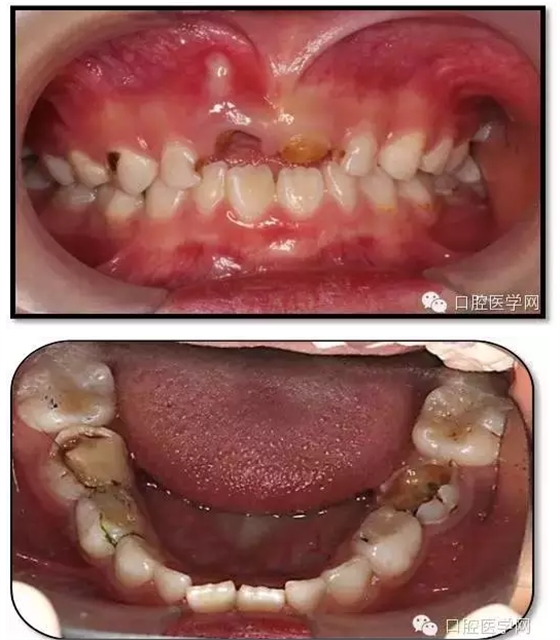

臨床檢查: 75OL齲洞, 舌側(cè)牙體完全劈裂斷端齊齦,探及大量軟化腐質(zhì)。頰側(cè)牙齦紅腫見瘺管,擠壓大量溢膿。叩(±),不松動。X線:75根管空虛,牙根吸收約1/2,根尖周及根分歧大面積透射影,35發(fā)育4期,骨硬板尚連續(xù);51殘根,唇側(cè)牙齦瘺管,叩(±),不松動。X線:51牙根吸收約1/2,根尖周低密度影。

85O、84DO充填體邊緣不密合,叩(±),不松動。84頰側(cè)牙齦略紅腫。X線:84遠(yuǎn)中根及髓室底完全吸收,根分歧透射影,近中根內(nèi)側(cè)見外吸收,44上方骨硬板連續(xù)。85近中根完全吸收,髓室底吸收,根分岐透射影,遠(yuǎn)中根管內(nèi)見根充影像。45發(fā)育4期,骨硬板連續(xù)。

診斷: 75OL、51、85O、84DO慢性根尖炎

65OL、74O中齲 55OL、53DL深齲

16OL、26O、36OB、46OB窩溝淺齲